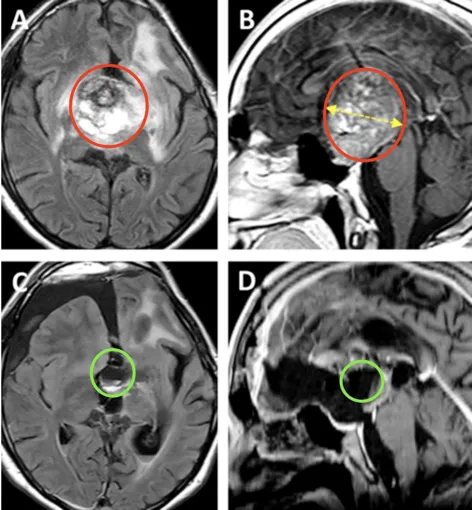

术前情况:MRI显示鞍区与丘脑存在巨大肿瘤,归类为Bcentral病变的复发性毛细胞星形细胞瘤,侵犯左侧海马旁回及侧脑室上部。肿瘤体积68.1 mm³,深度44.4 mm,侧面角21.9°。

术后情况:术后MRI显示肿瘤近全切,双侧大脑前动脉A2段灌注正常,视交叉、视神经束、垂体柄及下丘脑结构保全。